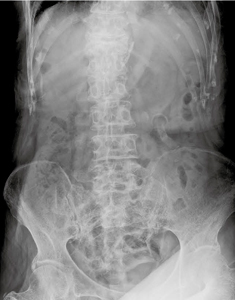

■Mobilett Miraによる臨床画像

検査目的:イレウス疑い |

長尾科長はグリッドなしの画質について,「胸部の画像はもちろんですが,より散乱線の多い腹部の撮影でも予想以上の画像が得られました。グリッド装着時の干渉による再撮影の可能性と,ポータブルの病棟撮影に求められる画質とを勘案し,病棟では基本的にグリッドなしで撮影を行うようになりました」と説明する。